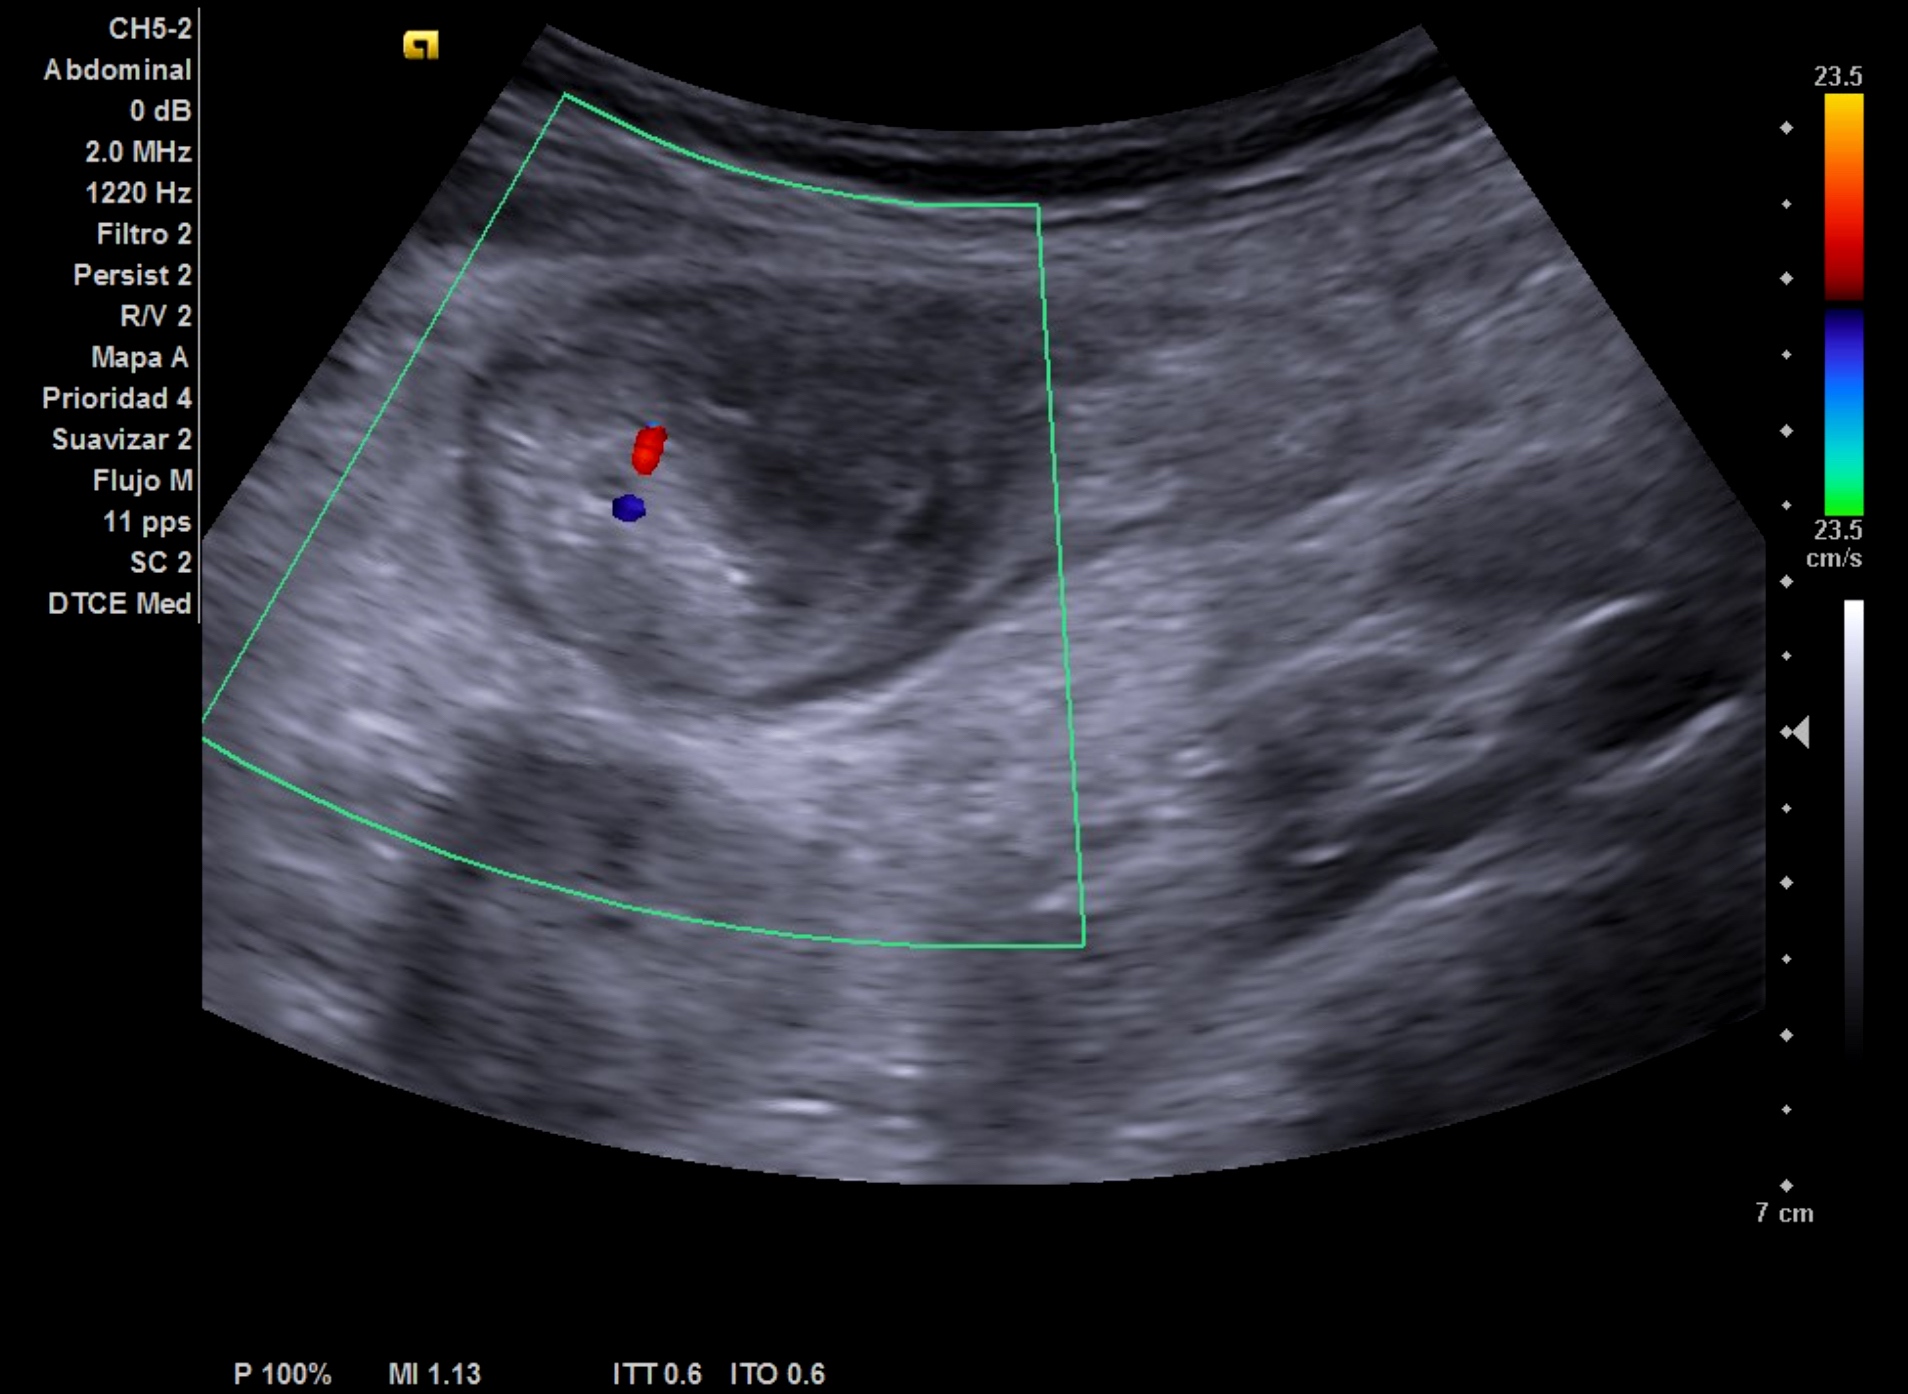

- Hígado de tamaño y eco-estructura normal. Riñón derecho normal. Imagen localizada anterior a riñón derecho, redondeada-ovalada, hipoecoica con zonas hiperecoicas en su interior, vascularizada probablemente compatible con signo de pseudo-riñón con sospecha de neoplasia de colon.